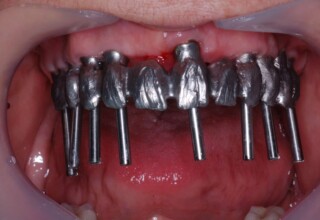

Lower jaw: extractions, direct implant placement and immediate loading (same day) with a transitional bridge.

Upper jaw: Sequential extractions, sequential implant placement and gradual incorporation in the temporary bridge so that the patient was never left without fixed teeth. The aim of the above approach was to have the patient in continuous functional and aesthetic reconstruction, without immediate loading due to anatomical restrictions. Old smiling photos of the patient were used because the natural shape of the teeth was completely lost due to repetitive prosthetic attempts. Tooth relationship and teeth-lip support was transferred to the temporary restorations. Two different transitional bridges were needed to fully estimate phonetics, mastication and esthetics. After the necessary adjustments were finalized, the temporary bridge was used as a guide for the permanent bridges.

Intermediate